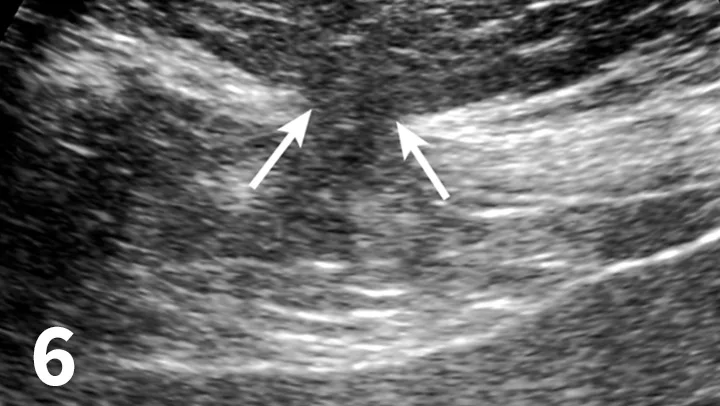

Featured Image

FIGURE 6

Ultrasound reveals a focal defect within the linea alba (arrows). Intra-abdominal fat extends through the defect into the subcutaneous tissues.

• CT and ultrasound may help differentiate a fluid pocket from presumed cellulitis or help locate an abdominal wall defect (Figure 6).